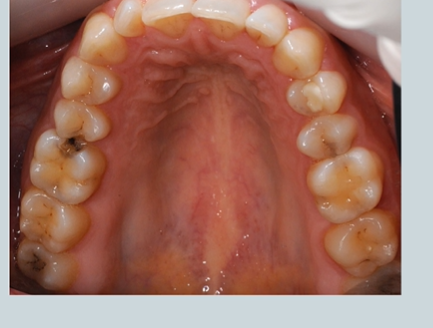

spot the caries

lower right and left second molars

are they the same colour? - the lower right has a fissure sealant

black one indicates staining and possible caries